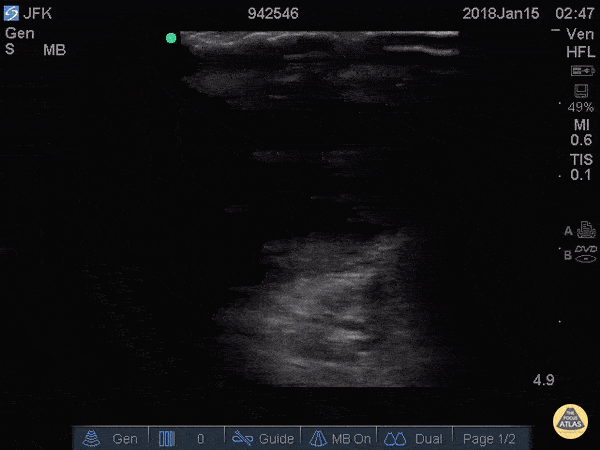

Renal/GU - Testicular Rupture

27 y/o M presented wit scrotal pain upon awakening after a night of heavy drinking. He could not recall any trauma. Physical exam revealed a tender, swollen, and ecchymotic scrotum. POCUS demonstrates hematocele, as well as (1) disruption of the tunica albuginea, (2) contour abnormality of the testis, and (3) heterogeneous echotexture of testicular parenchyma. These three findings collectively are highly sensitive and specific for testicular rupture1-3, and warrant urgent surgical exploration. Elizabeth Hanson, MD - EM resident, Kings County/SUNY Downstate 1. Deurdulian C, Mittelstaedt CA, Chong WK, Fielding JR. US of acute scrotal trauma: optimal technique, imaging findings, and management. RadioGraphics2007; 27: 357–369. 2. BuckleyJC, McAninch JW. Use of ultrasonography for the diagnosis of testicular injuries in blunt scrotal trauma. J Urol2006; 175: 175–178. 3. Micalle FM, Ahmad I, Ramesh N, Hurley M, McInerney D. Ultrasound features of blunt testicular injury. Injury2001; 32: 23–26.